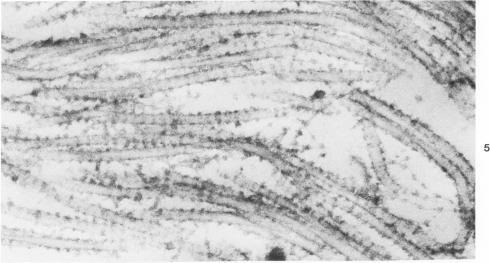

Injection of a solution of 30% urea in acetate buffer at pH 4.0 into the stroma of the uterine cervix results in a marked change in the mechanical properties of the tissue with subsequent easy dilatation. This study analyzes the changes in the collagenous matrix of the cervix by ultrastructural and biochemical methods. Collagen fibrils in urea-treated sections of the cervix are swollen and unravelled, showing spiral configuration of subunits in both cross-sections and longitudinal sections. The regular localization of ruthenium-red-positive material is absent in urea-treated tissues. Chemical analysis of incubated cervical tissues shows a reduction of the total glycosaminoglycans and of dermatan sulfate with release of the latter into the medium. It is suggested that urea dissociates intercollagen linkages by solubilizing a certain glycosaminoglycan, possibly dermatan sulfate. After this solubilization the collagen fibril is prompted to unwind, resolving the collagen microfibrils, which appear to be organized in a spiral fashion.

向子宫颈基质中注射pH 4.0的30%尿素醋酸盐缓冲溶液会导致组织力学性能发生显著变化,随后易于扩张。本研究通过超微结构和生化方法分析了子宫颈胶原基质的变化。经尿素处理的子宫颈切片中的胶原纤维肿胀且松散,在横截面和纵截面中均显示出亚单位的螺旋结构。经尿素处理的组织中钌红阳性物质的正常定位缺失。对孵育后的子宫颈组织进行化学分析表明,总糖胺聚糖和硫酸皮肤素减少,后者释放到培养基中。有人认为,尿素通过溶解某种糖胺聚糖(可能是硫酸皮肤素)来解离胶原间的连接。这种溶解后,胶原纤维会被促使展开,分解呈螺旋状排列的胶原微纤维。